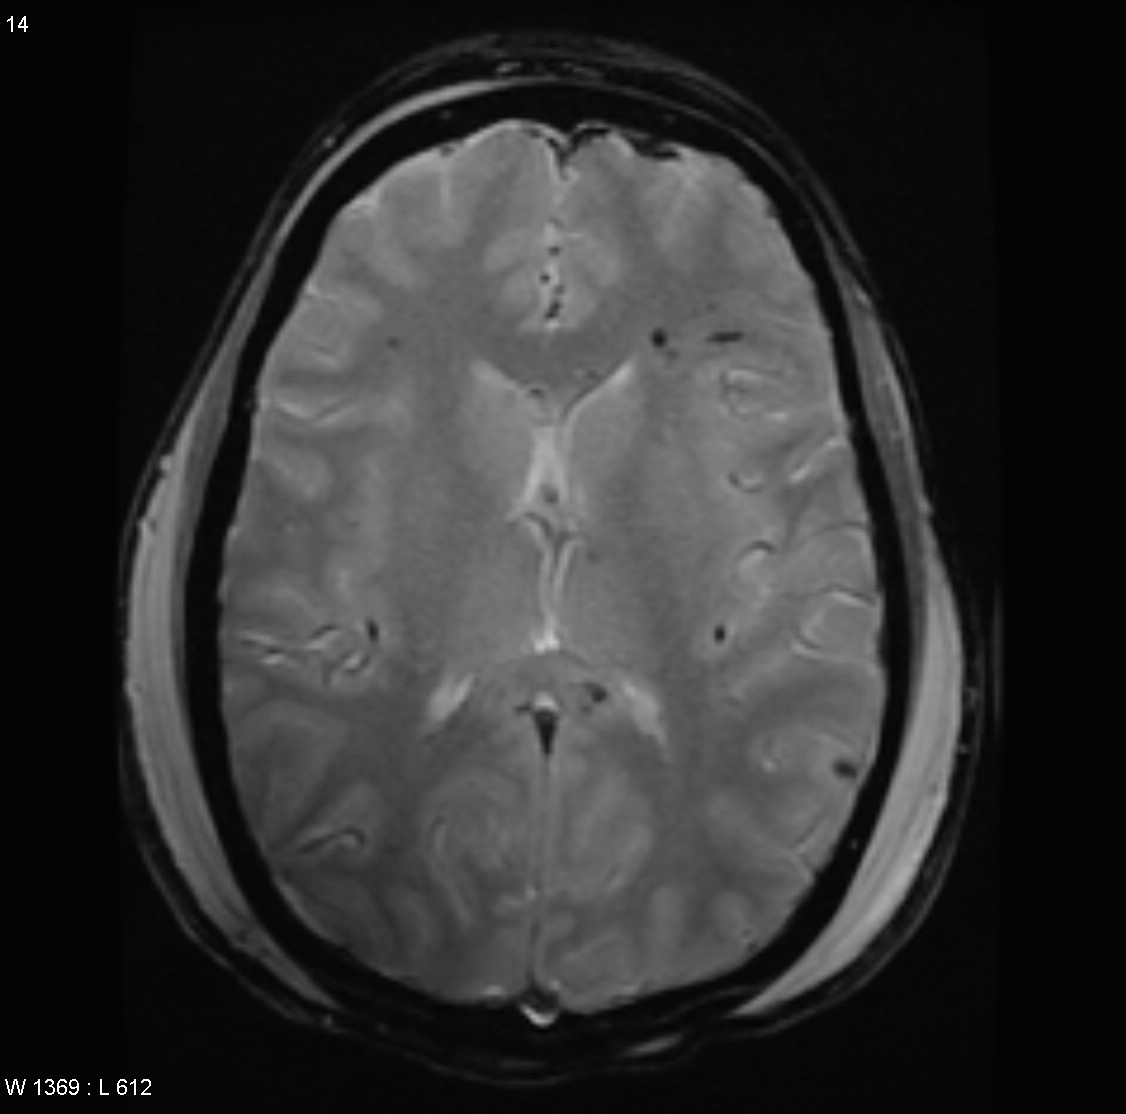

Note the multiple sites of oedema and haemorrhage, involving the brain stem and corpus callosum as well as subcortical white matter and left cerebral peduncle. High FLAIR signal is also seen in the dorsal midbrain. EVD insitu.

Case Discussion

Diffuse axonal injury can be subtle on CT but have devastating consequences for the patient. This is a case of grade III injury (involvement of brainstem) and carries a poor prognosis.

Diffuse axonal injury (DAI), also known as traumatic axonal injury (TAI), is a severe form of traumatic brain injury due to shearing forces. It is a potentially difficult diagnosis to make on imaging alone, especially on CT as the finding can be subtle, however, it has the potential to result in severe neurological impairment.

The diagnosis is best made on MRI where it is characterised by several small regions of susceptibility artifact at the grey-white matter junction, in the corpus callosum, and in more severe cases in the brainstem, surrounded by FLAIR hyperintensity.

Diffuse axonal injury is characterised by multiple focal lesions with a characteristic distribution: typically located at the grey-white matter junction, in the corpus callosum and in more severe cases in the brainstem (see: grading of diffuse axonal injury).

MRI is the modality of choice for assessing suspected diffuse axonal injury even in patients with entirely normal CT of the brain 5,6. MRI, especially SWI or GRE sequences, exquisitely sensitive to paramagnetic blood products may demonstrate small regions of susceptibility artefact at the grey-white matter junction, in the corpus callosum or the brain stem. Some lesions may be entirely non-haemorrhagic (even using high field strength SWI sequences). These will, however, be visible as regions of high FLAIR signal.